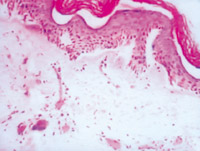

5-2-11 傷后第20天,大部分創(chuàng)面已由復(fù)層鱗狀上皮覆蓋,創(chuàng)面真皮層內(nèi)可見增生活躍的成纖維細(xì)胞和新生毛細(xì)血管  HE×100